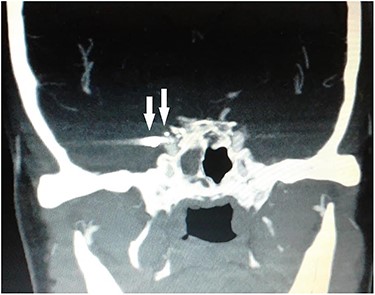

Computed tomography (CT) of the paranasal sinuses and angiography were requested on an urgent basis, which confirmed a diagnosis of pseudoaneurysm in her right CCA, adjacent to retained pellets (Figs 1–4). Also, her hemoglobin dropped from 11.5 to 8.4 gm over a 6-month period. Afterwards, she was referred to the interventional radiology department. She underwent stenting and coiling of her right internal carotid artery after which no further epistaxis happened for an uneventful year of follow-up.

Digital subtraction carotid angiography showing small hyperdense area in the right cavernous carotid artery.